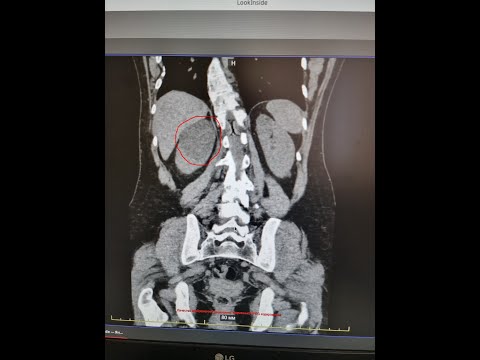

Laparoscopic Left Kidney cyst deroofing / Лапароскопическое иссечение кисты левой почкиСкачать

laparoscopic kidney cyst resection Лапароскопическая декортикация кисты правой почкиСкачать